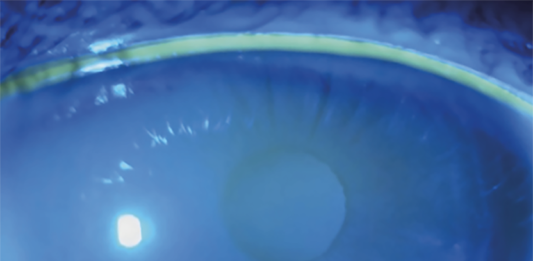

Il film lacrimale rappresenta una componente critica del sistema ottico, con una composizione estremamente complessa che include acqua, elettroliti, mucine e un ampio numero di proteine, lipidi e sostanze antimicrobiche.